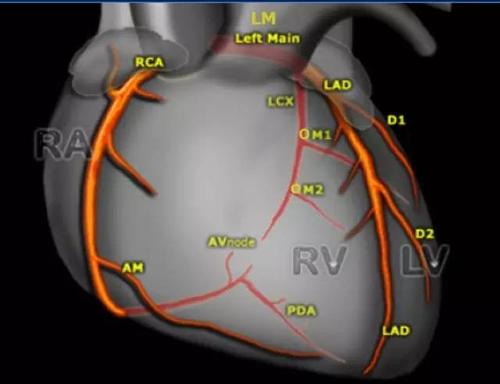

详细解读冠状动脉及冠心病ct

心脏ct断面解剖

带你全面了解心脏冠状动脉ct解剖

心脏解剖笔记:冠状动脉ct解剖及变异

冠脉图解

冠脉cta解剖图谱

冠脉循环图解

冠脉

心脏冠脉

心脏冠脉解剖示意图